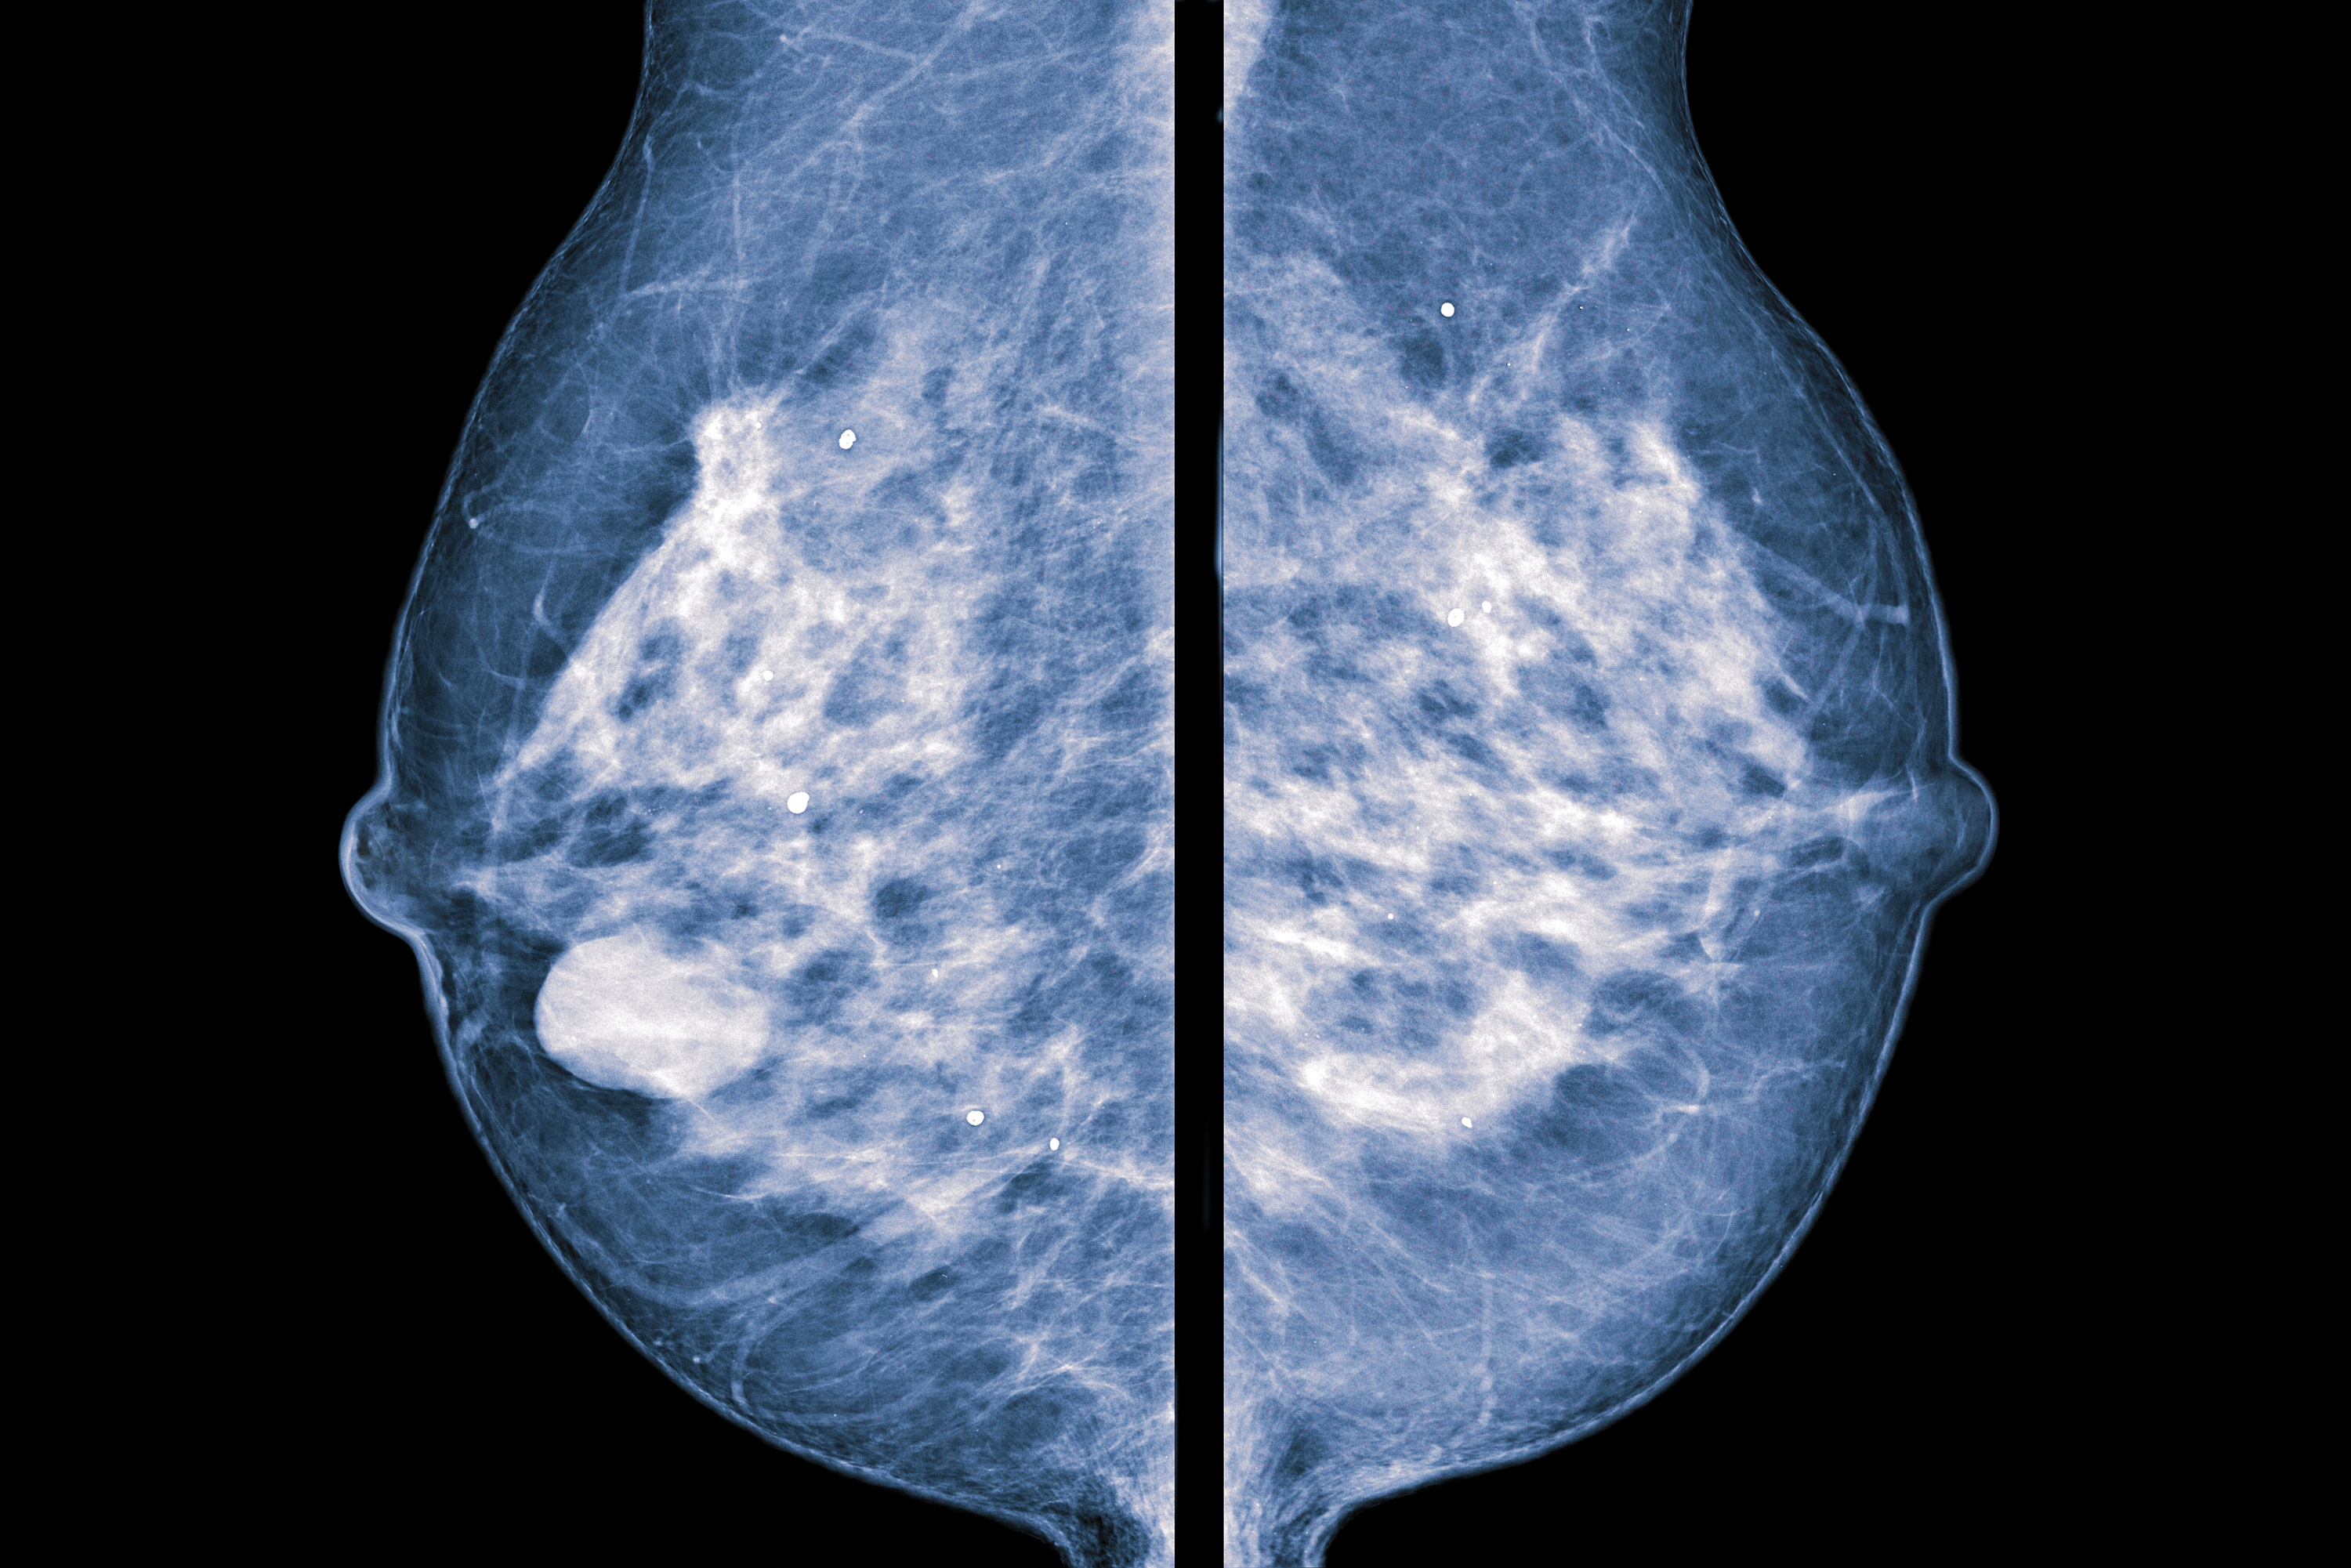

How to reduce calcification. Breast calcifications are calcium deposits that develop in breast tissue. Eating foods low in fat. While they’re usually benign (noncancerous), breast.

One of its functions is to transport excess calcium from places in. They’re common and often show up on a routine mammogram. The body controls the amount of calcium in the bloodstream very carefully.